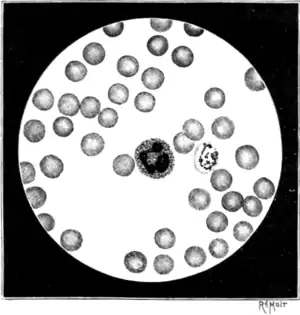

Fig. 16.—Microphotogram showing the necessary disposition of blood-corpuscles in slides for examination for the plasmodium. To the right of the white blood-corpuscle in the centre of the field a red blood-corpuscle three-fourths filled with a tertian parasite is visible (From microphotogram by Dr. Cosens.)